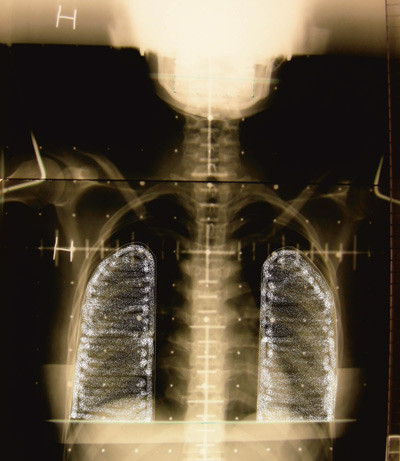

Hun hadde fått påvist Hodgkins sykdom i 1991 og ble da behandlet med cellegift og senere konsoliderende stråleterapi. Cellegift ble gitt i form av antracyklinet epirubicin totalt 360 mg, videre bleomycin, oncovin og dacarbazin (EBOD-kurer). Stråleterapi ble gitt som kappefelt, 23 behandlinger à 1,8 Gy, totalt 41,4 Gy. Strålefeltet inkluderte collum, supra- og infraklavikulære områder bilateralt og mediastinum inkludert hjertet (fig 1). Regelmessige kontroller avdekket ikke tegn til residiv.

Strålebehandling mot thorax ved Hodgkins sykdom eller andre kreftformer bedrer overlevelsen, men behandlingen kan blant annet gi utvikling av prematur koronarsykdom (6), klaffesykdom (7) eller kronisk perikarditt (8). Flere grupper har beskrevet sammenheng mellom tradisjonelle risikofaktorer og stråleterapi mot mediastinum for utvikling av kransåresykdom (9, 10). Selv om dette er historiske data, er de aktuelle fordi pasienter med Hodgkins sykdom har lang forventet levetid. I dag gis mer moderne stråleterapi med lavere totaldoser, men det er uavklart hvordan dette vil påvirke risikoen for utvikling av kransåresykdom. Vår pasient hadde familiær disposisjon for prematur koronarsykdom og røykte daglig. Det er nærliggende å anta at strålebehandlingen 15 år tidligere kan ha bidratt til den utbredte koronarsykdommen i en alder av bare 34 år. Karakteristiske forandringer i koronararteriene ved stråleskade er ostielesjoner både i venstre og høyre koronararterie, som hos vår pasient, og mer diffuse og lange stenoser med glatt overflate bedømt angiografisk (11).